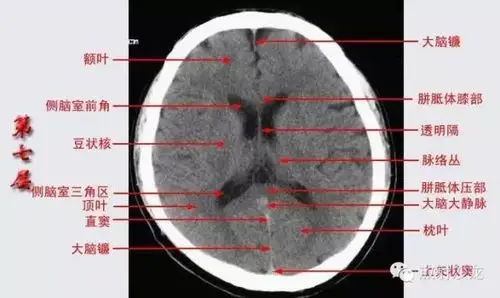

头颅ct断层解剖

影像医生必须掌握的头颅ct解剖与常见出血梗死判读

头颅ct解剖与常见出血梗死判读